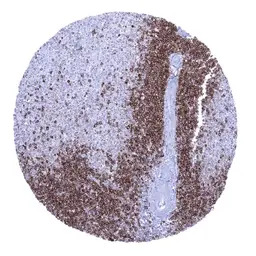

IHC-P analysis of human spleen tissue section using GTX04393 CD22 antibody [MSVA-022R] HistoMAX.

CD22 positive B lymphocytes predominate in the white pulp but are only sparse in the red pulp.